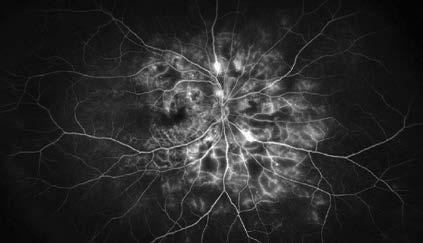

Figura 1. Imágenes de un paciente varón de unos 30 años con diabetes tipo 2 mal controlada (hemoglobina A1c >12%) y sin atención ocular previa. La angiografía con fluoresceína en la cita inicial mostró áreas extensas de ausencia de perfusión periférica con frondas de neovascularización (se muestra el ojo izquierdo). La OCT mostró edema macular diabético grave que afecta al centro (arriba, a la derecha) que respondió bien a las inyecciones intravítreas de anti-VEGF (aflibercept) (abajo, a la derecha). Un año después de la presentación, tenía 20/20 en ambos ojos con una A1c <7% debido a una mejor adhesión al cuidado de la diabetes y un mejor control sistémico de la glucosa.  Foto. Ian C. Han, MD.

Figura 4. Imagen de angiografía con fluoresceína de campo amplio del ojo derecho de un paciente con retinopatía diabética proliferativa, que muestra áreas hiperfluorescentes de tinción vascular y fuga junto con áreas hipofluorescentes de no perfusión Foto. Jason Hsu, MD.